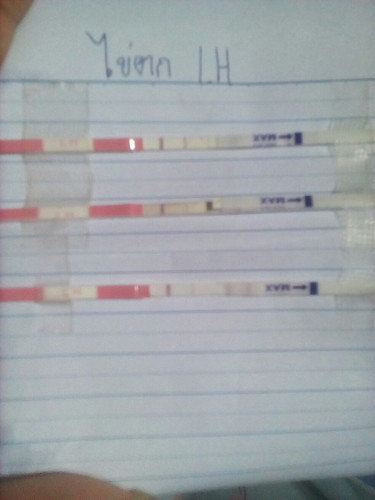

พึ่งมี ปจด ครั้งแรก ในรอบ1ปี10เดือน มีวันที่2หมดวันที่5 ด้วยความที่ไม่เคยใช้เทสไข่ตก เลยลองเทสดูเมื่อวันที่9 แล้วมาเทสอีกทีวันที่11และ14 แต่มันเข้มแค่วันที่9วันเดียว #อยากรู้ว่าไข่มันจะตกเร็วสุดกี่วัน (เหลือเทสอีก2อัน.จะลองตรวจวันพรุ่งนี้กับมะรืนดูอีก) เพิ่มเติม.ช่วงกลางดึกของวันที่9มีอาการหน่วงๆท้องน้อยค่ะ